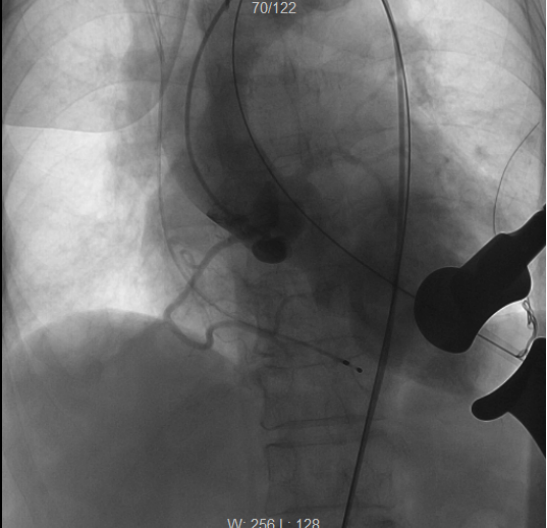

术前造影,提示主动脉瓣在舒张期出现大量返流

术后再次造影检查,见人工主动脉瓣位置良好,瓣口返流消失